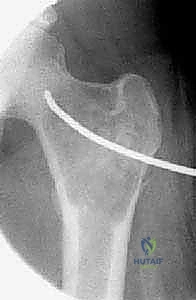

في الـ ABC، تظهر الآفة غير مركزية، متمددة، وتدفع قشرة العظم للخارج لتصبح رقيقة جداً مثل "قشرة البيضة".

تُظهر هذه الأشعة السينية كيس عظم متمدد (ABC). لاحظ التوسع الكبير في العظم وترقق القشرة العظمية مقارنة بالكيس أحادي الغرفة.